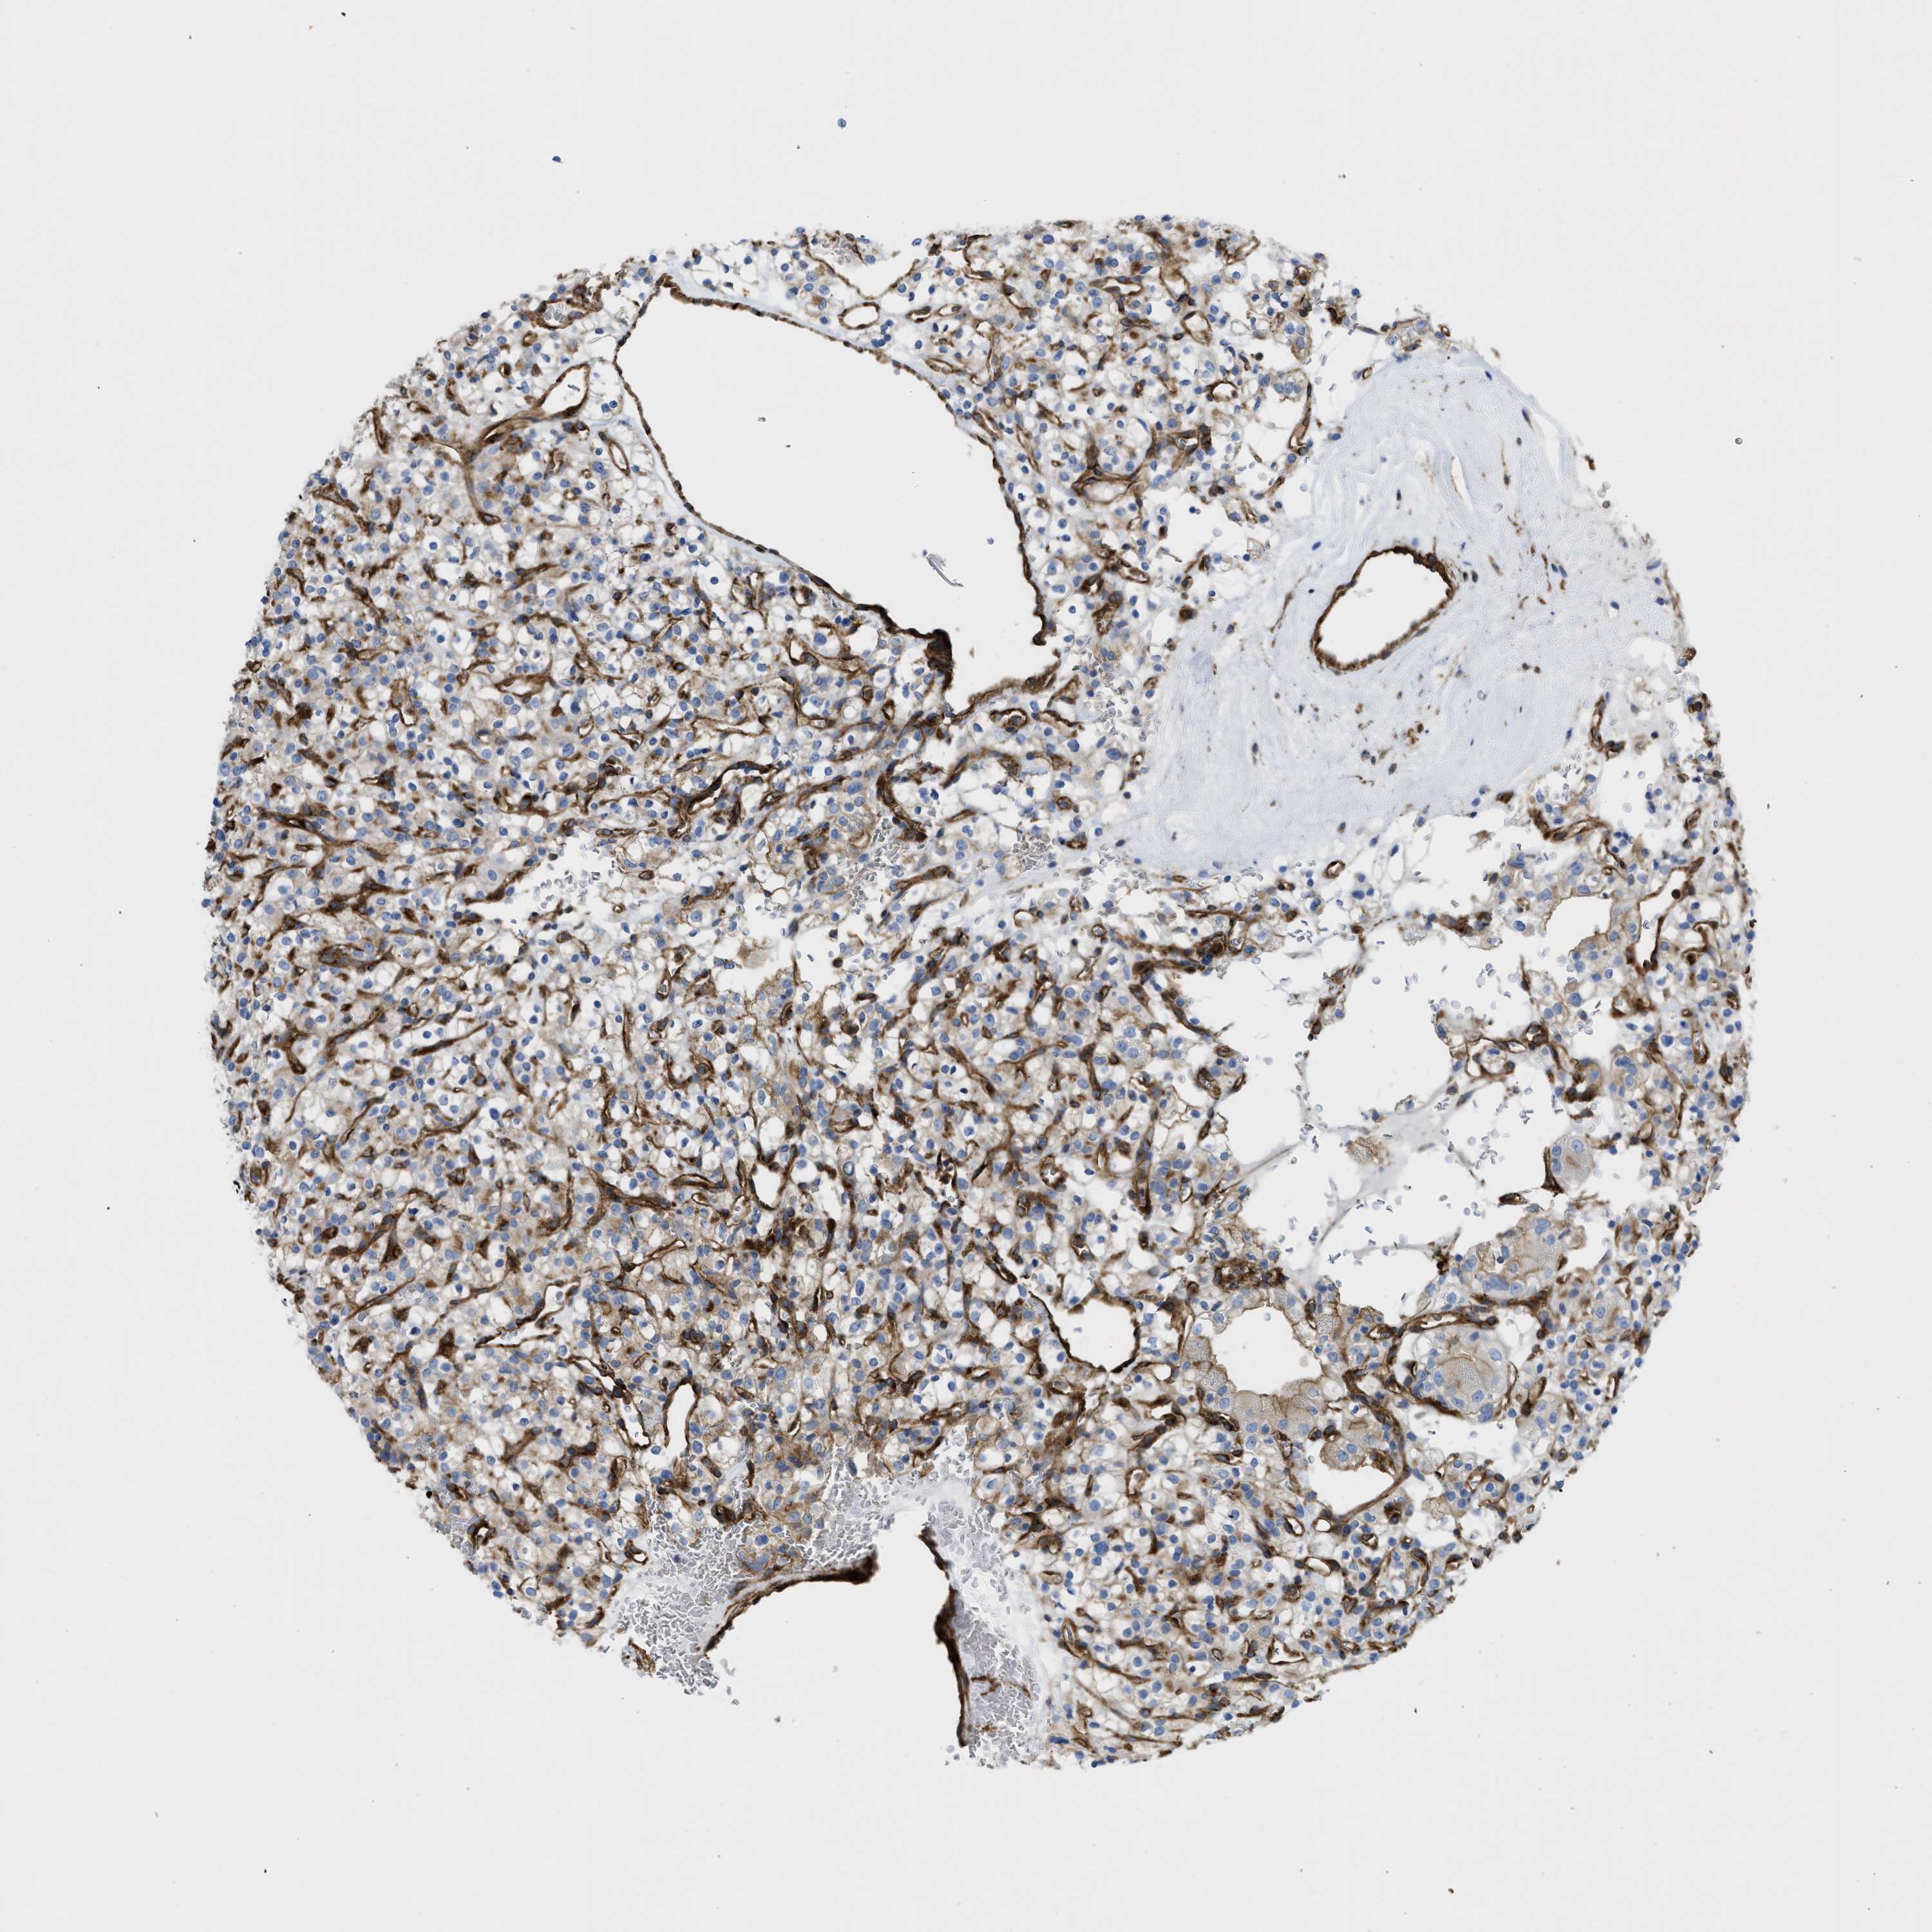

KIDNEY RENAL CLEAR CELL CARCINOMA (TCGA) - Interactive survival scatter ploti

The Survival Scatter plot shows the clinical status (i.e. dead or alive) for all individuals in the patient cohort, based on the same data that underlies the corresponding Kaplan-Meier plots. Patients that are alive at last time for follow-up are shown in blue and patients who have died during the study are shown in red.

The x-axis shows the expression levels (FPKM) of the investigated gene in the tumor tissue at the time of diagnosis. The y-axis shows the follow-up time after diagnosis (years). Both axes are complimented with kernel density curves demonstrating the data density over the axes. The top density plot shows the expression levels (FPKM) distribution among dead (red) and alive patients (blue). The right density plot shows the data density of the survived years of dead patients with high and low expression levels respectively, stratified using the cutoff indicated by the vertical dashed line through the Survival Scatter plot. This cutoff is automatically defined based on the FPKM cutoff that minimizes the p-score. The cutoff can be changed by dragging the vertical line or by entering a cutoff value in the square labeled "Current cut-off".

Under the Survival Scatter plot the p-score landscape (black curve; left axis) is shown together with dead median separation (red curve; right axis). Dead median separation is the difference in median mRNA expression between patients who have died with high and low expression, respectively. It is calculated as follows: median FPKM expression of dead patients with high expression - median FPKM expression of dead patients with low expression. This is intended to aid the user in visually exploring custom cutoffs and the associated p-scores and dead median separation.

Individual patient data is displayed and can be filtered by clicking on one or more of the category buttons on the top of the page. Categories describing expression level and patient information include: high, low, alive, dead, female, male and tumor stages. The scale of the x-axis can be toggled between linear and log-scale by clicking on the "x log" button. Mouse-over function shows TCGA ID, patient information and mRNA expression (FPKM) for each patient.

& Survival analysisi

Kaplan-Meier plots summarize results from analysis of correlation between mRNA expression level and patient survival. Patients were divided based on level of expression into one of the two groups "low" (under cut off) or "high" (over cut off). X-axis shows time for survival (years) and y-axis shows the probability of survival, where 1.0 corresponds to 100 percent.

HIP1 is validated prognostic, high expression is favorable in Kidney Renal Clear Cell Carcinoma (TCGA)

Best expression cut offi

Based on the FPKM value of each gene, patients were classified into two groups and association between prognosis (survival) and gene expression (FPKM) was examined. The best expression cut-off refers the FPKM value that yields maximal difference with regard to survival between the two groups at the lowest log-rank P-value. Best expression cut-off was selected based on survival analysis .

When clicking on this number, the vertical dashed line indicating cut-off, the interactive survival plot, and the Kaplan-Meier curve will be adjusted to show results based on the best expression cut-off.

: 19.66

TCGA RNA samplesi

RNA-seq data is reported as average FPKM (number Fragments Per Kilobase of exon per Million reads), generated by the The Cancer Genome Atlas (TCGA) .

Normal distribution across the dataset is visualized with box plots, shown as median and 25th and 75th percentiles. Points are displayed as outliers if they are above or below 1.5 times the interquartile range. FPKM values of the individual samples are presented next to the box plot.

Average pTPM 17.3

Number of samples 521